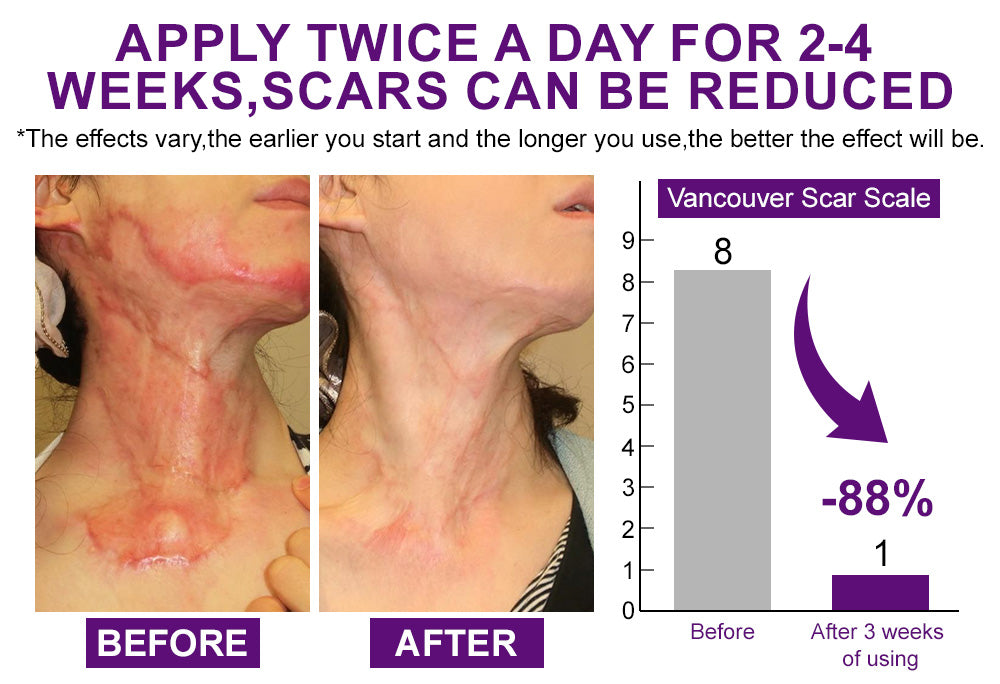

"The effect is remarkable. I had a severe burn on my chest years ago, and the scar tissue was thick, red and made me avoid certain clothes. The gel arrived well packaged and on time. The texture is light, almost silky, and absorbs quickly without any sticky residue. I applied it twice a day, morning and evening, as recommended. Within just a few weeks, the redness started to fade and the tightness eased. After three months, the scar looks flatter, softer, and much less noticeable. Truly worth it." - Emily Clarke, London

"The effect is remarkable. I had a severe burn on my chest years ago, and the scar tissue was thick, red and made me avoid certain clothes. The gel arrived well packaged and on time. The texture is light, almost silky, and absorbs quickly without any sticky residue. I applied it twice a day, morning and evening, as recommended. Within just a few weeks, the redness started to fade and the tightness eased. After three months, the scar looks flatter, softer, and much less noticeable. Truly worth it." - Emily Clarke, London "After abdominal surgery, I was left with a long scar that made me avoid beaches and swimming pools. I applied a thin layer twice a day, making sure to cover the whole line. The gel dries quickly so I could dress right after without stains. At first, I wasn’t expecting much, but around the 6th week I noticed the line getting lighter and smoother. After two months, it’s almost flat and blends with my skin. This gel honestly gave me back confidence I thought I’d lost forever."

"After abdominal surgery, I was left with a long scar that made me avoid beaches and swimming pools. I applied a thin layer twice a day, making sure to cover the whole line. The gel dries quickly so I could dress right after without stains. At first, I wasn’t expecting much, but around the 6th week I noticed the line getting lighter and smoother. After two months, it’s almost flat and blends with my skin. This gel honestly gave me back confidence I thought I’d lost forever."

Scars can appear in many forms — hypertrophic scars that rise within the wound area, firm keloids that grow beyond the injury, atrophic scars like acne marks or chickenpox depressions, post-surgical or trauma scars from C-sections or accidents, and even burn or contracture scars that tighten the skin and restrict movement. No matter the type, scars often cause redness, itching, tenderness and tightness, which not only bring physical discomfort but also affect self-confidence and daily mobility.

Scars can appear in many forms — hypertrophic scars that rise within the wound area, firm keloids that grow beyond the injury, atrophic scars like acne marks or chickenpox depressions, post-surgical or trauma scars from C-sections or accidents, and even burn or contracture scars that tighten the skin and restrict movement. No matter the type, scars often cause redness, itching, tenderness and tightness, which not only bring physical discomfort but also affect self-confidence and daily mobility.

Don’t Let Scars Hold You Back Any Longer.

Don’t Let Scars Hold You Back Any Longer.

💡 Tip: Apply twice daily for best results — morning and night. Stay consistent, and watch your scars gradually fade into smoother, softer, more confident skin.

💡 Tip: Apply twice daily for best results — morning and night. Stay consistent, and watch your scars gradually fade into smoother, softer, more confident skin.